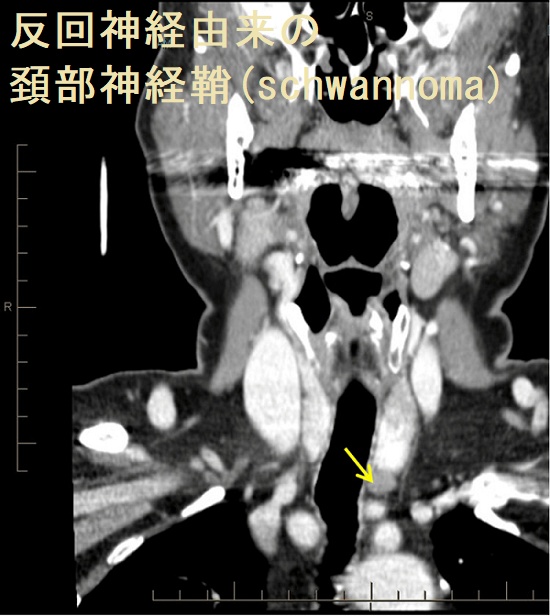

頚部神経線維腫は迷走神経/反回神経・交感神経幹・腕神経叢から発生。超音波(エコー)画像上、紡錘形で内部血流を認めないのが特徴。

頚部神経鞘腫(schwannoma)は硬く、血流に乏しい腫瘤で、発生母体の神経(写真では迷走神経)に連続しています。

- 充実性、均一エコー型(solid pattern);エラストグラフィーでは硬い

- 不均一エコー型(multiple microcystic pattern)

- 辺縁増強を伴う嚢胞型(cystic pattern)

があります(耳鼻34:677 ~683 ,1988.)。